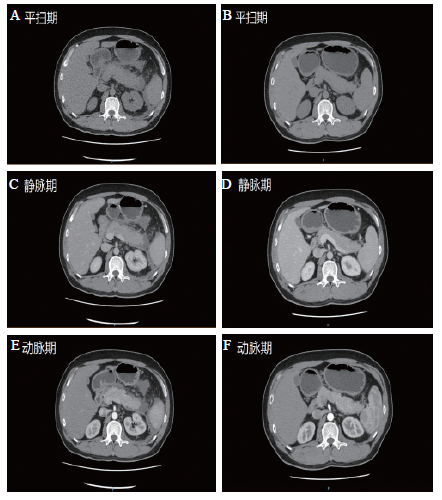

入院诊断:腹痛查因。入院后进一步完善相关检查:甲状腺功能FT3降低(2.66 pmol/L),FT4降低(5.24 pmol/L),TSH 升高(5.87 mIU/L)。血清免疫球蛋白及补体增高(lgG 17.38 g/L,IgA 5 g/L,λ-免疫球蛋白轻链2.39 g/L,补体C4 457 mg/L),lgG4正常,自身抗体及其他风湿免疫指标均阴性。血促肾上腺皮质激素(ACTH)正常(8、16、0时分别为 46.5、24.5、21.5 pg/ml),血皮质醇增高(8、16、0时分别为726.53、506.09、473.35 nmol/L), 24 h尿游离皮质醇明显增高(2463.08 nmol/24 h),垂体激素及性激素均正常。CA199升高(44.76 U/L),其他肿瘤标志物正常。13C呼气试验阳性。胃镜检查显示慢性胃炎,肠镜检查显示结肠多发息肉。腹部增强CT显示胰腺体尾部肿胀、体积增大,密度稍减低,其周围、左膈下、左上腹、脾周可见积液,增强扫描胰尾部可见坏死不强化区,未见明显增强延迟,影像诊断为急性出血坏死性胰腺炎(图1A)。其他:垂体MR、心电图、泌尿系统彩超、甲状腺彩超、甲状腺静态显像及肾上腺彩超等未见明显异常。

图1 AP伴免疫及内分泌系统变化患者治疗前后腹部CT对比

A、C、E:治疗前腹部增强CT显示胰腺体尾部肿胀、体积增大,其周围、左膈下、左上腹、脾周可见积液,胰尾部可见坏死区;B、D、F:8周后复查腹部增强CT显示胰腺体尾部周围渗出、积液等较前明显减少

根据临床表现及相关检查,临床诊断为AP (中度);免疫功能及甲状腺激素、皮质醇异常查因。予禁食、补液、抗感染、醋酸奥曲肽抑制胰腺分泌等治疗。2周后症状明显改善,复查炎症(血常规、超敏CRP)、内分泌(甲功五项、ACTH、血皮质醇、24 h尿游离皮质醇)、免疫(血清免疫球蛋白及补体)、白蛋白、CA199明显好转,3周后再次复查上诉指标基本恢复正常。8周后复查炎症(血常规、超敏CRP)、内分泌(FT3、FT4、TSH、ACTH、血皮质醇)、ESR、IgG、胆固醇、白蛋白、CA199均正常,甘油三酯仍较高(7.0 mmol/L),同时复查腹部增强CT显示胰腺体尾部周围渗出、积液等较前明显减少(图1B)。最后诊断:AP(中度,酒精性及高甘油三酯性)伴免疫及内分泌系统变化;慢性胃炎;结肠多发息肉。